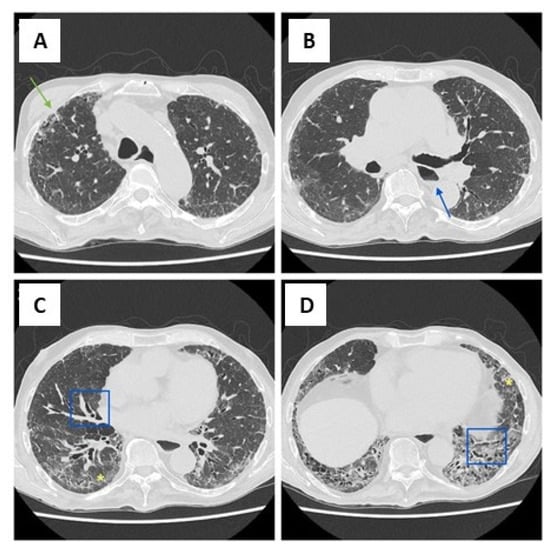

- Robledo, G.C.; Hernández, M.Y.J.; Lucas, S.A.G.; Delgado, F.R.C. Combined Pulmonary Fibrosis and Emphysema With Pulmonary Hypertension: Cases Report. Curr. Probl. Cardiol. 2022, 47, 100856. [Google Scholar] [CrossRef] [PubMed]